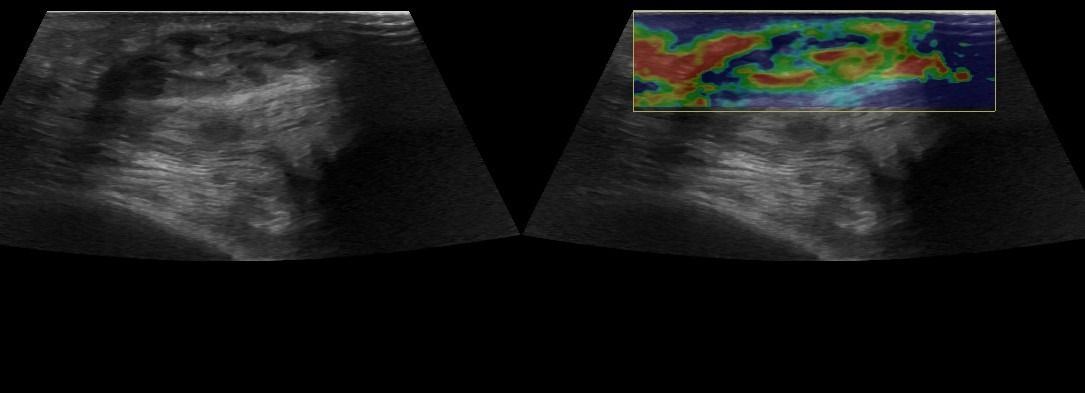

Η τεχνική του Έγχρωμου Doppler μελετάει την αγγείωση της βλάβης. Η τεχνική του Παλμικού Doppler μελετάει την παρουσία αρτηριακών ή φλεβικών στοιχείων εντός της βλάβης. Επίσης πολύ χρήσιμη είναι η Ελαστογραφική Μελέτη η οποία μελετάει τη σκληρότητας της βλάβης. Οι τεχνικές αυτές μας βοηθούν να χαρακτηρίσουμε αν η βλάβη είναι αγγειακού τύπου και αν έχει καλοήθη η ύποπτα χαρακτηριστικά.